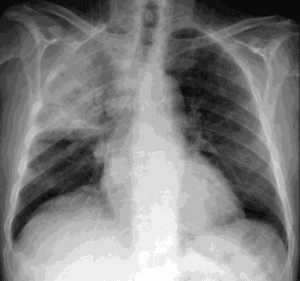

This is a routine outpatient chest x-ray that just showed up on your list at 4:45 pm on a Friday. What is the appropriate management?

Call the referring provider right away. Don’t risk the report sitting in their inbox until Monday.

We’re all familiar with critical findings that need to be communicated immediately like strokes or PEs, but it is also important to communicate more “routine” findings in a way that would prevent delays in treatment that could cause significant adverse outcomes.

Takeaway: Consider potential treatment delays in how you choose to communicate your findings.